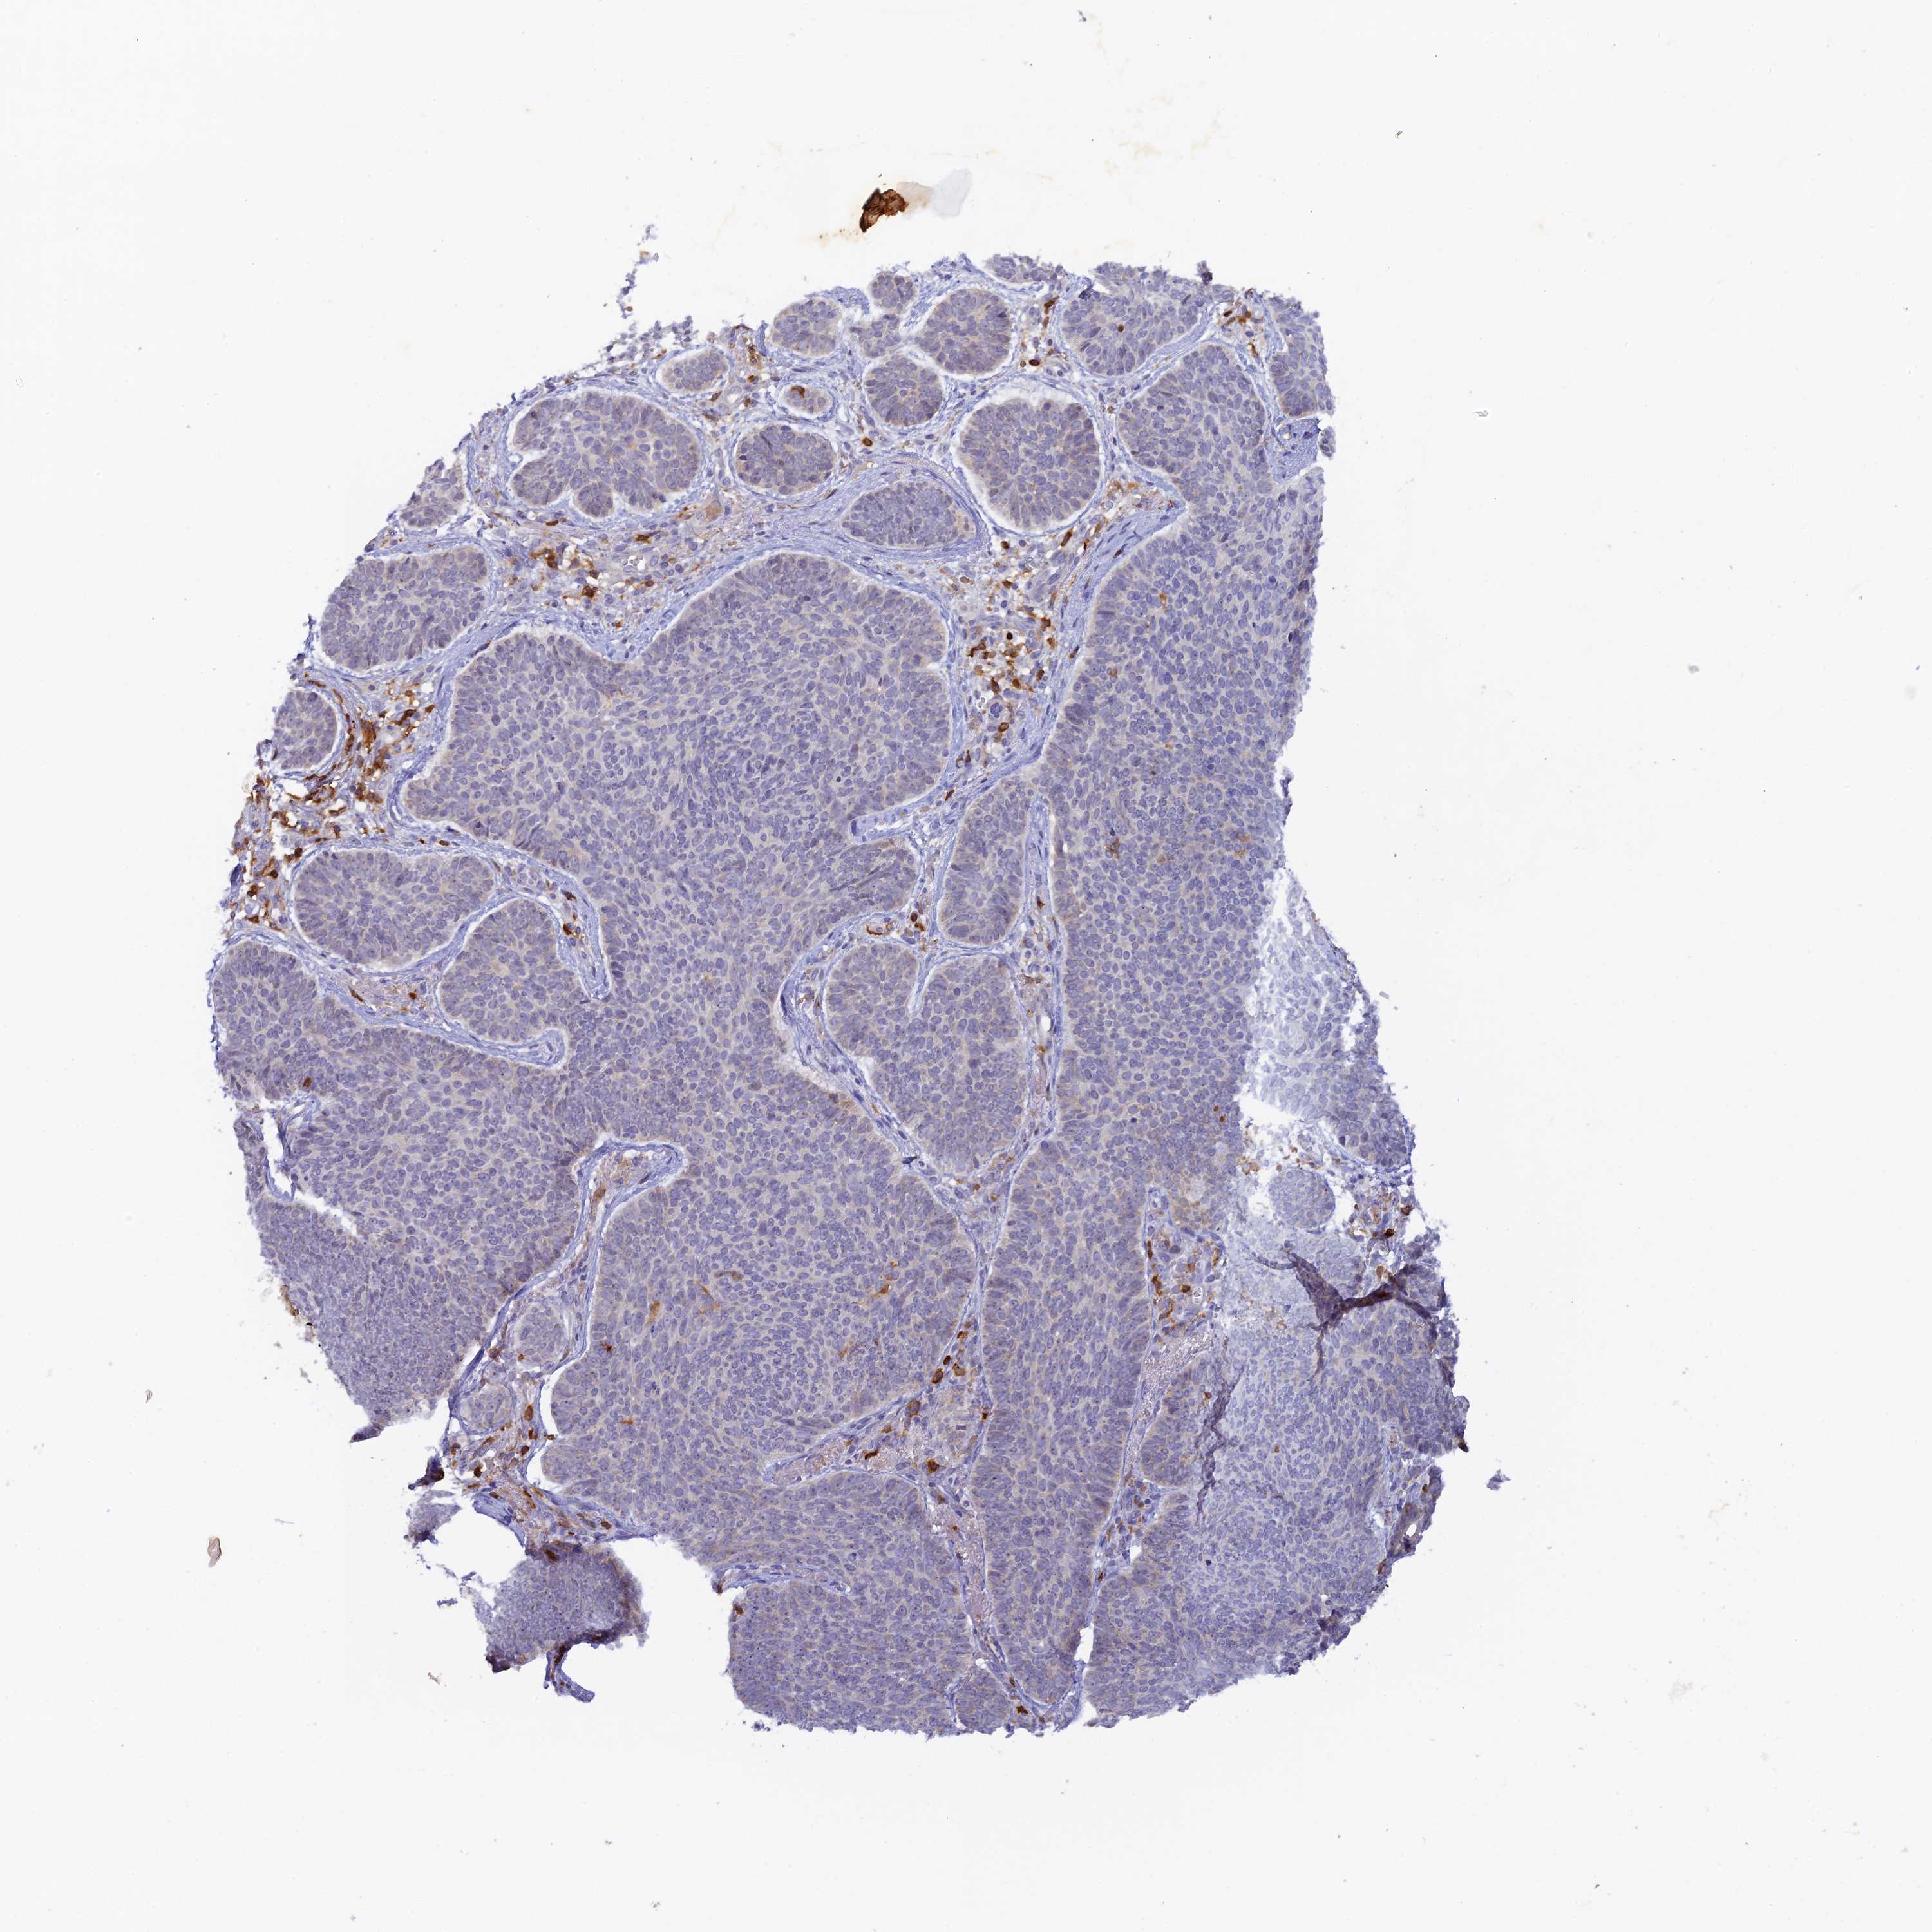

SKIN CANCER - Protein expressioni

A mouse-over function shows sample information and annotation data. Click on an image to view it in a full screen mode. Samples can be filtered based on level of antibody staining by selecting one or several of the following categories: high, medium, low and not detected. The assay and annotation is described here.

Antibody staining in the annotated cell types in the current human tissue is reported as not detected, low, medium, or high, based on conventional immunohistochemistry profiling in selected tissues. This score is based on the combination of the staining intensity and fraction of stained cells.

Each image is clickable and will lead to virtual microscopy that enables deeper exploration of all samples and also displays staining intensity scores, fraction scores and subcellular localization as well as patient and tissue information for each sample.

Antibody HPA026796

Basal cell carcinoma